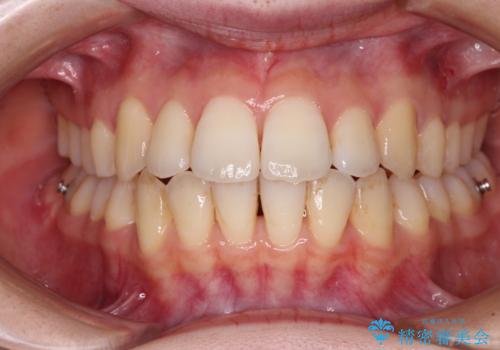

【モニター】前歯の前突感とクロスバイトをインビザラインで改善

- 前歯の突出感とクロスバイトが気になり、インビザラインによる矯正治療を希望して来院された患者様です。

舌側転位している側切歯特有の、切縁の位置が不揃いであったり、根元が内側に引っ込んだ状態であったりという、インビザライン独特の仕上がりになることなく、きれいに整った歯列とすることができました。